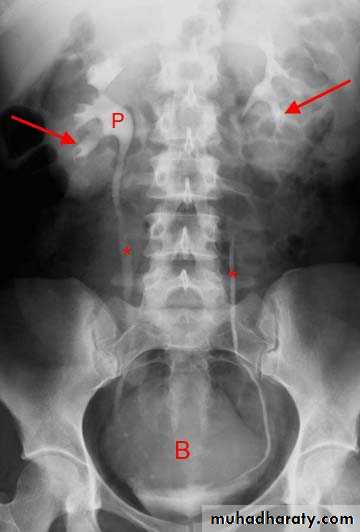

1.Nephrogram phase (Immediately after injection of contrast) .

2. Pyelogram Phase(l-5 minutes after injection of contrast) .3. After 10 minutes with compression, to get better distention of the pelvis and calyces.

4. Full length film after release of compression .

5. A full bladder film (with the urinary bladder fully distended with contrast)

4. Bladder

The bladder is a centrally located structure.

Smooth in outline.

Smooth indentation from above by uterus on the right or sigmoid colon on the left and from below by muscles of the pelvic floor is normal.

Other than that, any filling defect, wall irregularity or diverticula must be carefully looked for.